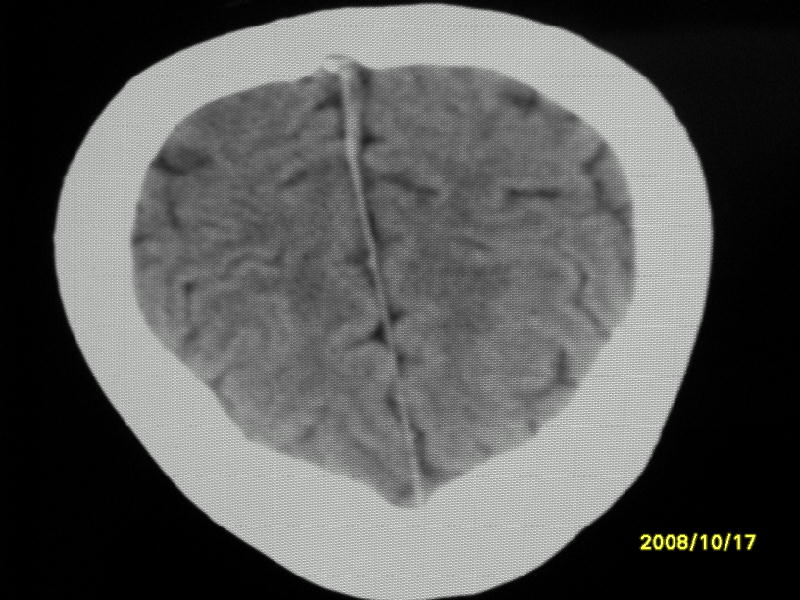

检查名称:     ct颅脑平扫           男     28岁

表现:左顶叶见斑点状致密影。边缘清,大小约0。3*1。0cm,余脑实质密度及灰白质结构示见异常。脑室系统大小,形态,密度未见异常。脑沟。脑裂。脑池未见异常密度影。中线结构无移位。

印象:左顶叶少许钙化灶

左顶叶见斑点状致密影。边缘清,大小约0。3*1。0cm,余脑实质密度及灰白质结构示见异常。脑室系统大小,形态,密度未见异常。脑沟。脑裂。脑池未见异常密度影。中线结构无移位。

印象:左顶叶少许钙化灶。

镰旁钙化

镰旁钙化或顶骨内板骨嵴部分容积效应,建议mri矢状位扫描观察与顶骨的关系。排外后者。